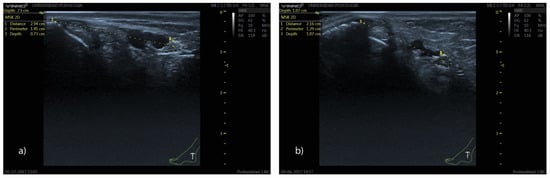

2.3. Ultrasound Protocol

- Distance (D): from the most prominent point of the medial malleolus to the center of the TN.

- Depth (d): perpendicular distance from the skin surface to the upper edge of the tibial nerve perimeter.

- Perimeter (P): measured along the outer contour of the TN.

- TN–PTA relationship: classified according to the relative position of both structures.